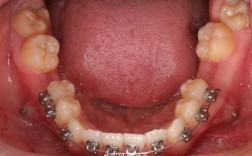

- 陶瓷托槽矫正: 美观度较好,托槽接近牙齿颜色。

- 自锁托槽矫正: 复诊间隔可能延长,舒适度相对较好,效率可能更高。